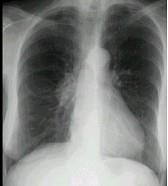

问题 男,67岁,无明显症状,胸片检查发现病变,进一步行CT检查如图,其最可能的诊断为 ( )

选项 A.右下肺炎性假瘤 B.右下肺周围型肺癌 C.右下肺错构瘤 D.后纵隔神经源性肿瘤 E.右侧胸膜间壁瘤

答案 D